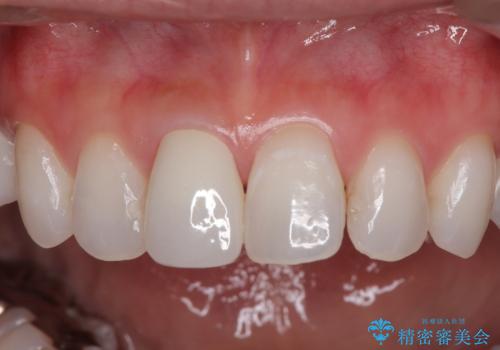

- 前歯の変色と、以前装着したクラウンが黄ばんできたことを気にして来院された患者様です。

まずは根管治療を行い、痛みの消退を確認してからオールセラミッククラウンによる補綴治療を行うこととしました。

黄ばんできてしまった小臼歯部のクラウンは、根尖部に症状を認めないため、そのままオールセラミッククラウンによる補綴治療を行うこととしました。

色がやや白いと感じましたが、ご自身でホームホワイトニングをされているそうで、今後周辺の歯を白くしていくとのことでした。